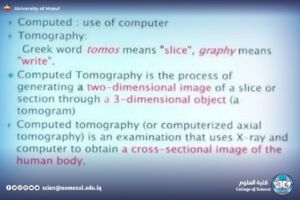

CT: شرح لكيفية أخذ مقاطع متعددة، وفكرة الـHU، ودوره في تصوير الدماغ والبطن والرئة.